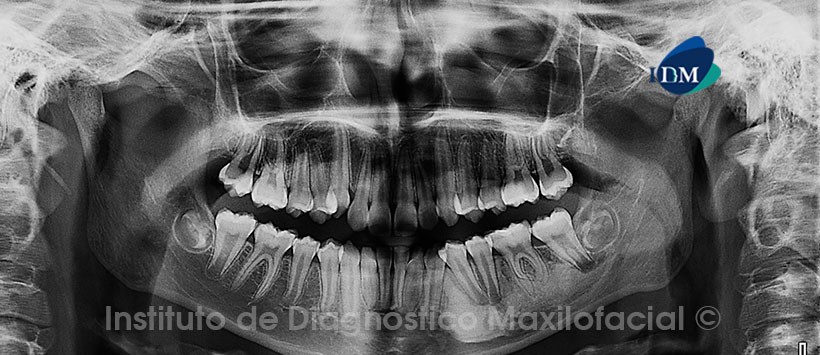

Paciente masculino, 11 años de edad es referido al Instituto de Diagnostico Maxilofacial (IDM) para evaluación general.

A la evaluación de la radiografía panorámica (ortopantomografía) se aprecian los gérmenes dentarios de las piezas 18, 28, 38 y 48 en evolución interósea; así como una raíz supernumeraia en la pieza 36. Además de la presencia de una imagen radiopaca en cuerpo mandibular izquierdo de limites definidos sin aparente compromiso de estructuras óseas. (Figura 1)